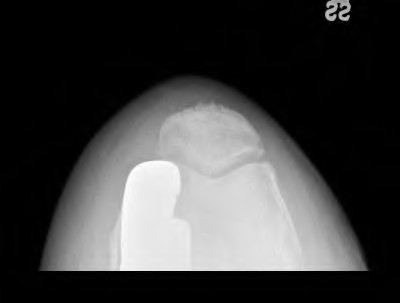

A 72-year-old female presents with progressive left thigh and knee pain for the last year. 5 years ago she sustained a femoral neck fracture treated with the implant seen in Figures A-C (current radiographs). The thigh pain is worse with weight-bearing. C-reactive

protein and erythrocyte sedimentation levels are within defined limits. Which of the following is the most likely cause of her pain?